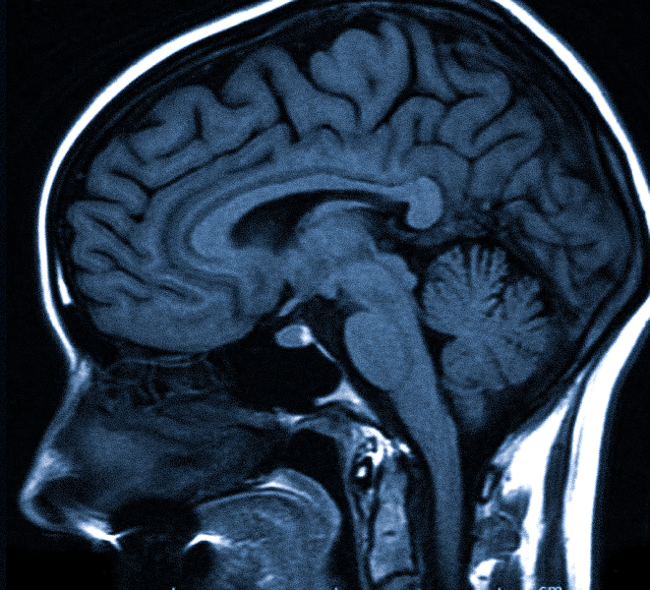

Если вы не знакомы с этим тестом, МРТ использует магнитное поле и радиоволны, чтобы сделать подробные снимки ваших внутренностей.

По данным клиники Мэйо, когда вы находитесь внутри аппарата МРТ, его магнитное поле временно перестраивает атомы водорода в вашем теле. Радиоволны заставляют эти атомы создавать очень слабые сигналы, которые используются для создания изображений поперечного сечения.Эти изображения накладываются друг на друга, чтобы врачам было действительно хорошо видно ваше тело изнутри, которое они могут видеть под разными углами.

«Он обеспечивает отличную анатомическую детализацию мягких тканей, что полезно для оценки конкретных условий», — объясняет она.

По данным клиники Майо, МРТ позволяет выявить широкий спектр проблем, включая аномалии дисков в позвоночнике, проблемы с суставами, опухоли в различных органах, таких как почки и яичники, структурные проблемы в сердце и травмы головного мозга.